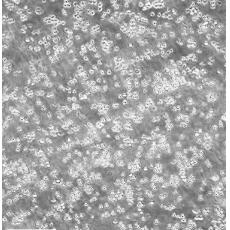

MOLT-4

中文名稱 人急性淋巴母細(xì)胞白血病細(xì)胞

組織來(lái)源 急性T淋巴細(xì)胞白血病;男性

生長(zhǎng)特性 suspension

形態(tài)特征 lymphoblast

細(xì)胞描述 MOLT-4與MOLT-3來(lái)源于一名19歲的男性急性淋巴細(xì)胞性白血病的復(fù)發(fā)患者,該患者前期接受過(guò)多種藥物聯(lián)合化療。MOLT-4細(xì)胞系為T淋巴細(xì)胞起源,p53基因的第248位密碼子有一個(gè)G→A突變,不表達(dá)p53,不表達(dá)免疫球蛋白或EB病毒;可產(chǎn)生高水平的末端脫氧核糖轉(zhuǎn)移酶;表達(dá)CD1(49%),CD2(35%),CD3A(26%)B(33%)C(34%),CD4(55%),CD5(72%),CD6(22%),CD7(77%)。